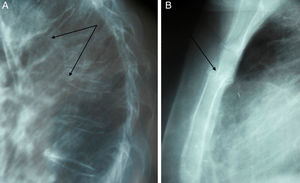

Caso clínicoMujer de 41 años, que acudió al servicio de urgencias con dolor osteomuscular generalizado, especialmente en el tórax, la columna y las ingles. Las radiografías iniciales mostraron múltiples fracturas, en el esternón a nivel del tercio superior del cuerpo esternal, dos fracturas vertebrales dorsales severas o de grado 3 y una tercera fractura dorsal de grado 1-2, y de rama isquiopubiana (fig. 1A y B). En la exploración posterior se halló hipertensión arterial y rasgos cushingoides, como facies de luna llena y obesidad central.